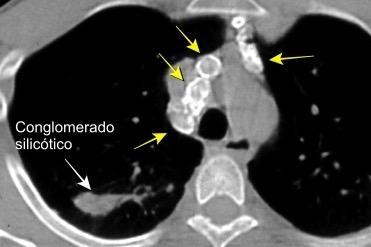

Silicosis secundaria al pulido con chorro de arena. Tejidos ”Denim”. (vaqueros, etc.)

Marchiori E et al. Conglomerated masses of silicosis in sandblasters: High-resolution CT findings. Eur Radiol 2006

Alper F,, et al. CT findings in silicosis due to denim sandblasting. Eur Radiol. 2008

Conglomerado silicótico